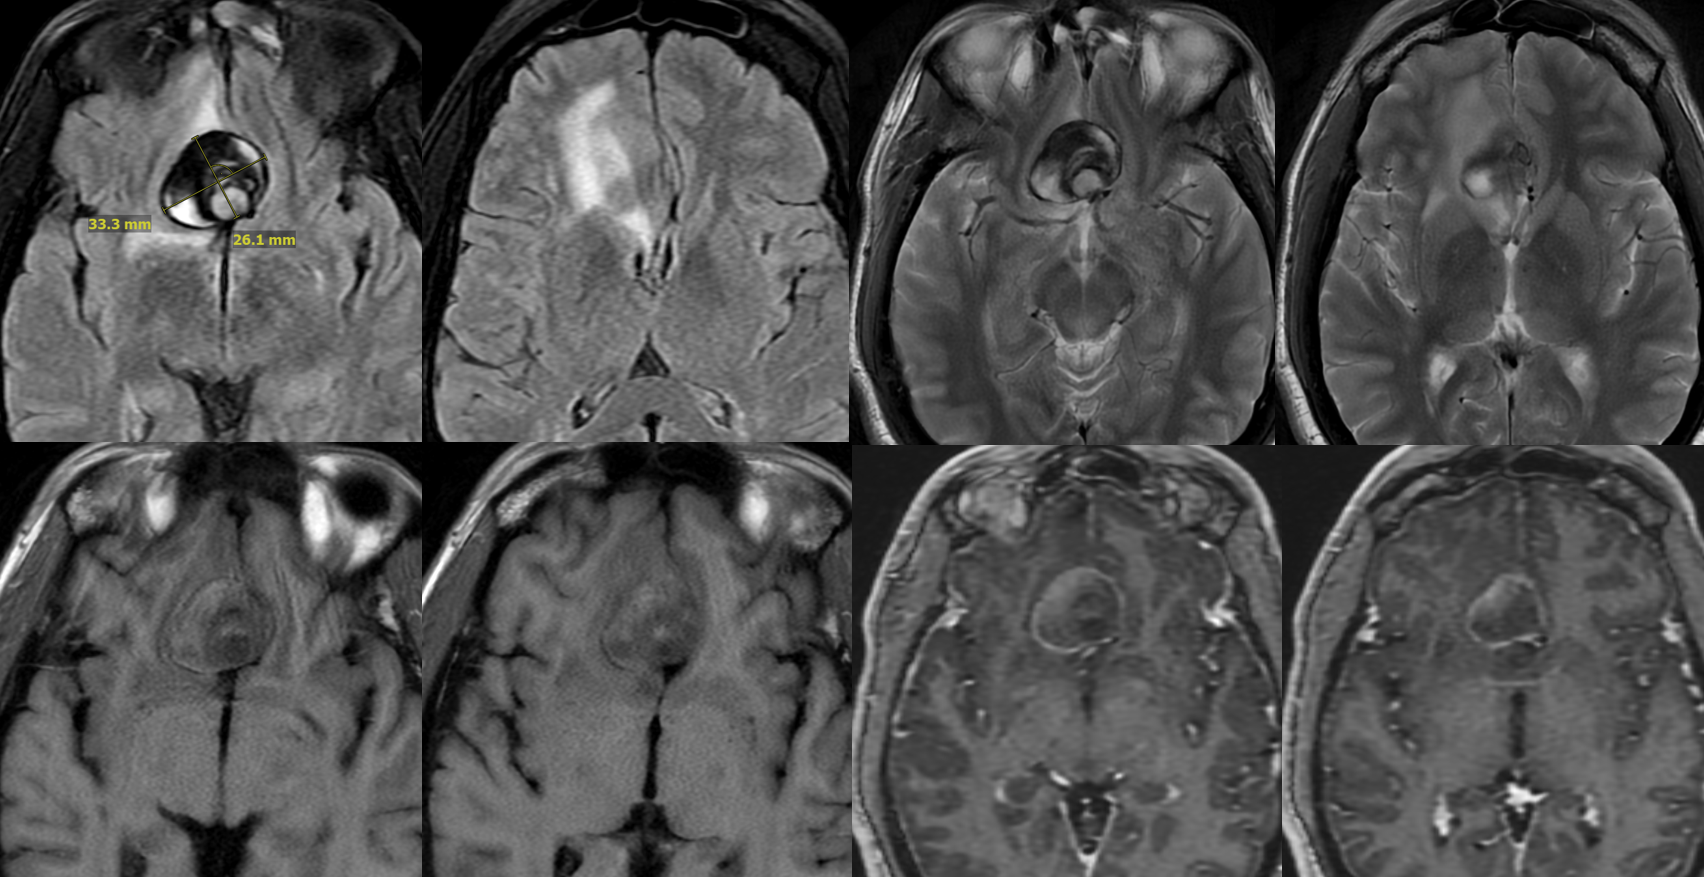

Giant ACOM

More problems? Yes

So far, we have a giant mostly thrombosed ACOM aneurysm with adjacent edema, a chronically occluded right cervical ICA, and right ACA dependent on the ACOM flow… Not easy

A secondary reconstruction and detailed analysis is better. What does arrow point to?

1 mo later — open portion is larger despite same medication regimen